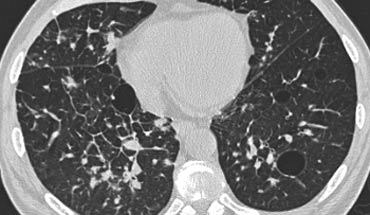

Bệnh nhân này nhập viện với triệu chứng khó thở cấp tính và phim X-quang ngực bình thường (không trình bày).

HRCT lúc nhập viện (trái) cho thấy các vùng kính mờ theo phân bố tiểu thùy.

HRCT kiểm tra mười ngày sau (phải) cho thấy các tổn thương đã thoái lui hoàn toàn mà không cần điều trị.

Các tổn thương được cho là do viêm phổi quá mẫn.